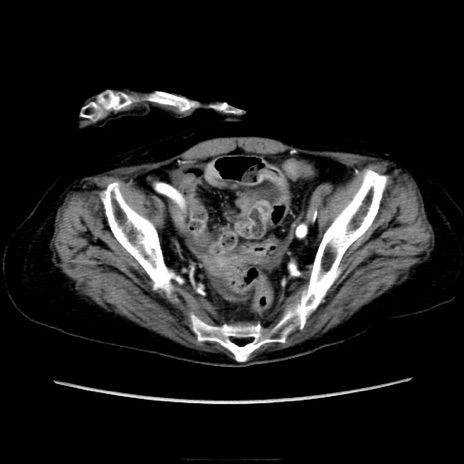

症例40(横断像)

【症例】90歳代女性

【主訴】腹痛・嘔吐

【現病歴】 食欲低下、嘔吐があり昨日他院受診。肺炎と診断され入院となる。入院後より腹部全体に圧痛あり。胃管留置され経過みていたが、症状持続するため、

当院転院となる。

【既往歴】胸椎圧迫骨折、胆石症

【身体所見】腹部:中央に激痛あり、圧痛あり、反跳痛不明

【データ】WBC 17100、CRP 18.82

横断像